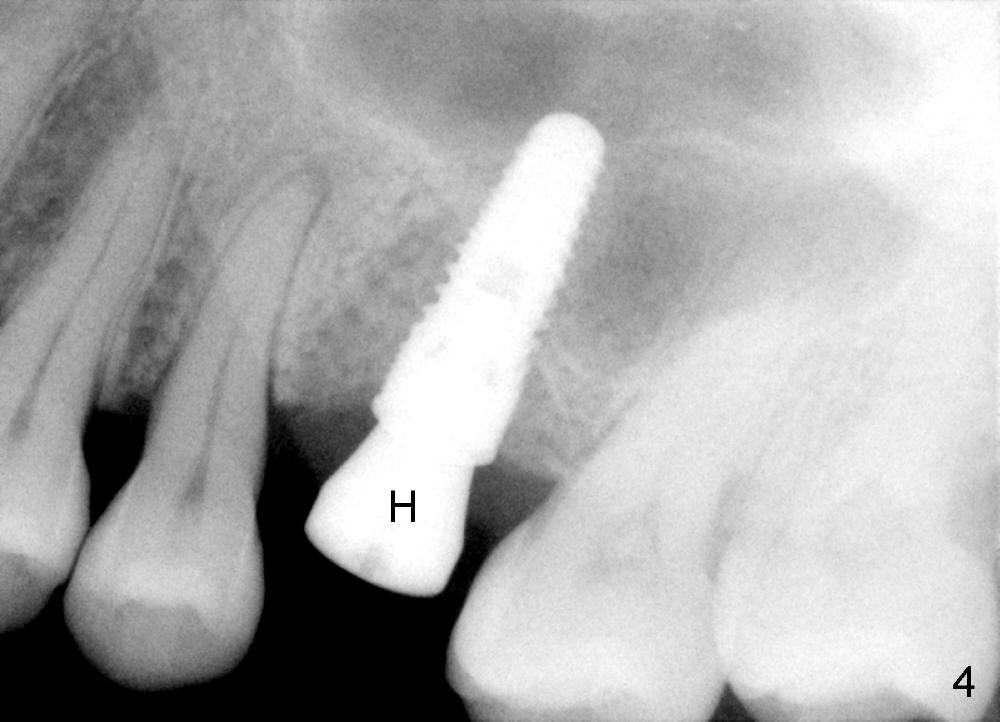

Fig.4 is taken 3.5 months postop. There is some bone surrounding the apex of the implant.